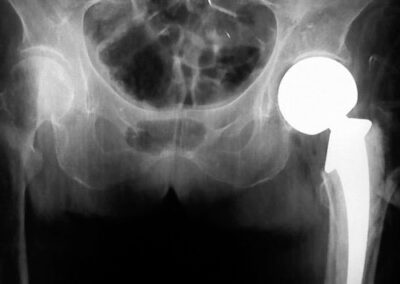

Exemplos de artroplastia cimentada e não-cimentada podem ser vistos na Fig. 2, através das radiografias. A figura ainda mostra exemplos radiográficos de artroplastias híbrida (haste femoral cimentada e componente acetabular não-cimentado) e híbrida-reversa (haste femoral não-cimentada e componente acetabular cimentado). O sucesso da artroplastia total de quadril depende basicamente de três fatores críticos: escolha do paciente, do implante e da técnica cirúrgica. Provavelmente, o determinante isolado mais importante seja a escolha apropriada do paciente. A escolha de um paciente inadequado pode comprometer o design mais avançado ou mesmo o cirurgião mais experiente (1,2,7).